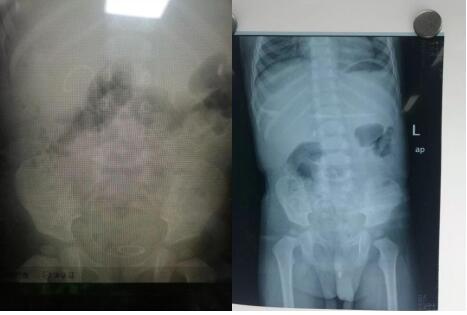

成人导航泌尿外科成功为一岁半患儿实施 尿道结石钬激光碎石术